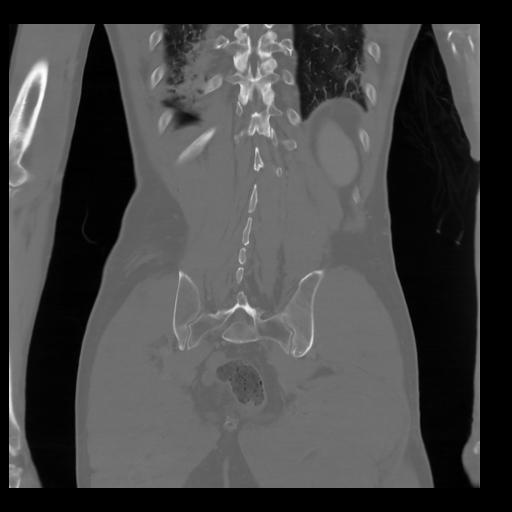

35 CUERPO,CE,Coronal,3.000,CUERPO,Coronal,